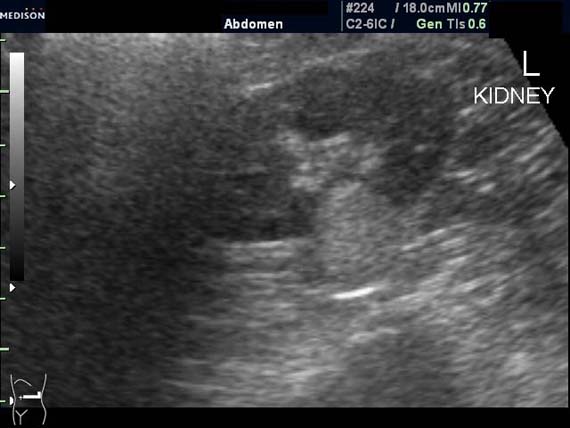

Женщина 50 лет. Жалоб нет. Обследование перед поездкой в санаторий по поводу дисфункции гепатобилиарной системы.

Случайная находка в нижней трети левой почки (не в полюсе, а по задне-медиальной поверхности).

ПО УЗ-семиотике образование соответствует ангиомиолипоме (AML). По правилам в таких случаях необходимо выполнить КТ, доказать преимущественно жировой состав опухоли, затем проводить УЗ-наблюдение.

Согласен. Именно с таким диагнозом (ангиомиолипома) отправил на КТ. Особенностью случая ИМХО является заметный "выход" образования за контур почки (на 2/3 объема).

При ультрасонографии ангиомиолипома выглядит как округлое образование без капсулы с однородной внутренней эхоструктурой и четкими контурами; эхогенность ее чаще всего равна или чуть выше эхогенности перинефральной клетчатки [7]. Значительно реже эхогенность ангиомиолипом может быть равна эхогенности почечной паренхимы; такие опухоли состоят почти полностью из гладкомышечной ткани [8]. Иногда позади ангиомиолипомы может определяться слабая акустическая тень.